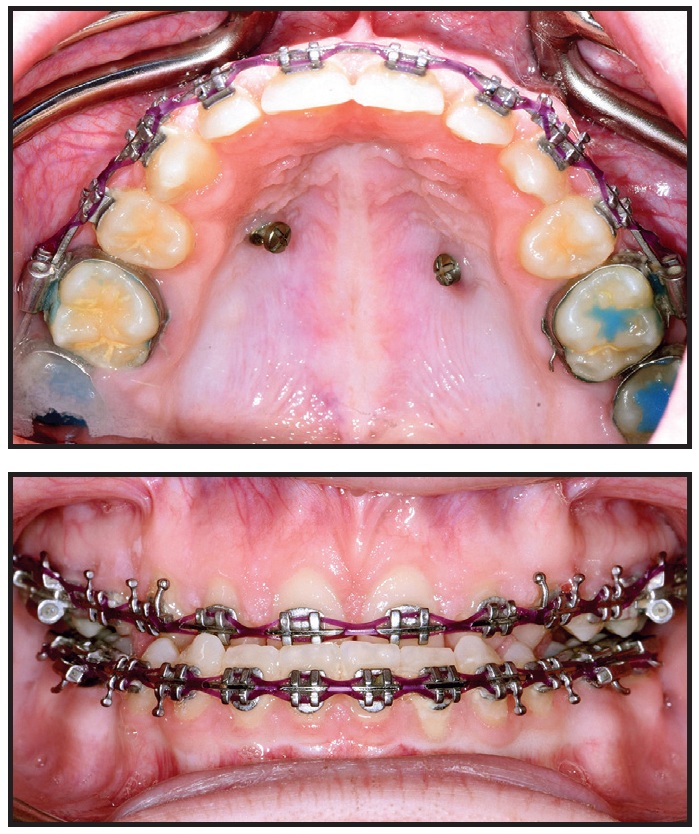

This patient presented with rotations from canine to canine in both arches (Fig. 5A). After 10 months of clear aligner therapy, the most severe rotation (the lower left lateral incisor) had been corrected, but a minor derotation of the lower right lateral incisor was still needed for ideal alignment (Fig. 5B). Even after an extra set of aligners, the rotation of the lower right lateral incisor was still unresolved (Fig. 5C).

Fig. 5 A. Patient with rotations from canine to canine in both arches before treatment. B. After 10 months of clear aligner therapy, minor rotation of lower right lateral incisor remaining. C. After extra set of aligners, rotation of lower right lateral incisor still unresolved.

Although premature contacts are easily ignored in an orthodontic practice, they can have serious effects on the tooth structure and support. Routine three-dimensional intraoral scans can easily show us where they are located. In this case, there was a strong contact between the upper right central incisor and lower right lateral incisor (Fig. 6). This contact should have been adjusted before more aligners were fabricated, but the premature contact with the distal marginal ridge of the upper right central incisor was clearly preventing derotation of the lower right lateral incisor (Fig. 7).

At this point, a selective occlusal adjustment was performed, and the rotations were entirely corrected with a few additional aligners.

It is not always possible to avoid premature anterior contacts due to the desired tooth positions or anatomy, the tooth-movement plan, or many other treatment-related factors. Nevertheless, occlusal contacts should be checked regularly in all cases. Every clinician should become familiar with the occlusal-adjustment techniques that will enable maximum intercuspation.

Fig. 6 3D intraoral scan showing strong contact between upper right central incisor and lower right lateral incisor.

Fig. 7 Premature contact with upper right central incisor’s distal marginal ridge prevents derotation of lower right lateral incisor.